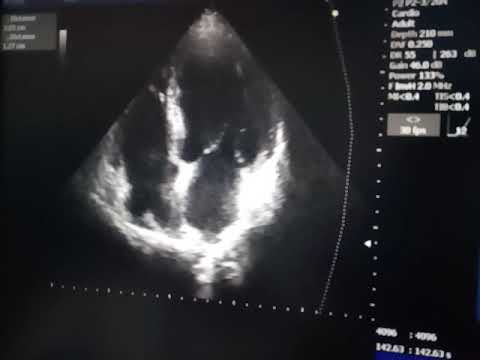

Ребенок 2 лет, со слов сопровождающего наблюдается с диагнозом ДКМП (дилатационная кардиомиопатия). На текущем УЗИ ЛЖ не расширен (КДРЛЖ 28мм, N для ППТ=0,5 до 32 мм), Тейхольц ФВ (фракция выброса) 65%, Симпсон ФВ 40-48%, миокард ЛЖ имеет извитой внутренний контур (диф.диагноз: некомпактный миокард, др.), клапанные регургитации: 1 ст на ЛК(легочном) и АК(аортальном), 2-3 ст. на ТК(трикуспидальном) и МК(митральном). Подробнее:

#узи #эхокг Pediatric Cardiac ultrasound - Non-compact and valvular regurgitaions Child 2 years-old, according to the mother observed with DCM (dilated cardiomyopathy). At the current ultrasound left ventricle is not enlarged (LVEDD 28mm, N for BSA = 0.5 to 32 mm), Teichholz EF (ejection fraction) 65%, Simpson EF 40-48%, left ventricular myocardium has a curved inner border (dif.diag.: non-compacted myocardium, etc.). Also were are valvular regurgitations: stage 1 on the PV(pulmonary) and AV(aortic) and of 2-3 stage at TV(tricuspidal) and MV(mitral). More: